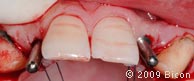

25. Внешний вид после извлечения временных протезов.